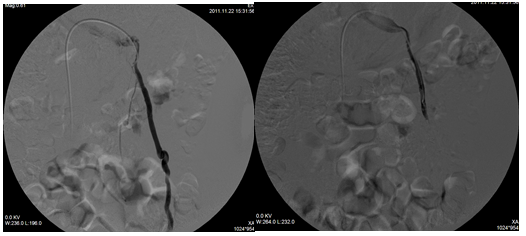

精索静脉曲张是男性不育的常见原因之一,传统的手术采用的是高位结扎血管的方法,由于曲张的精索静脉解剖结构复杂,常容易出现漏扎而导致手术失败。并且手术方法创口较大,术后常出现阴囊水肿、血肿等并发症。介入治疗是微创方法,创口小,痛苦少,因其可以准确地了解血管的结构,选择最合适部位栓塞。

典型病例:男、18岁,患左侧精索静脉曲张无法通过征兵体检,术后恢复良好,第二年顺利通过了体检,圆了自己的军旅梦!